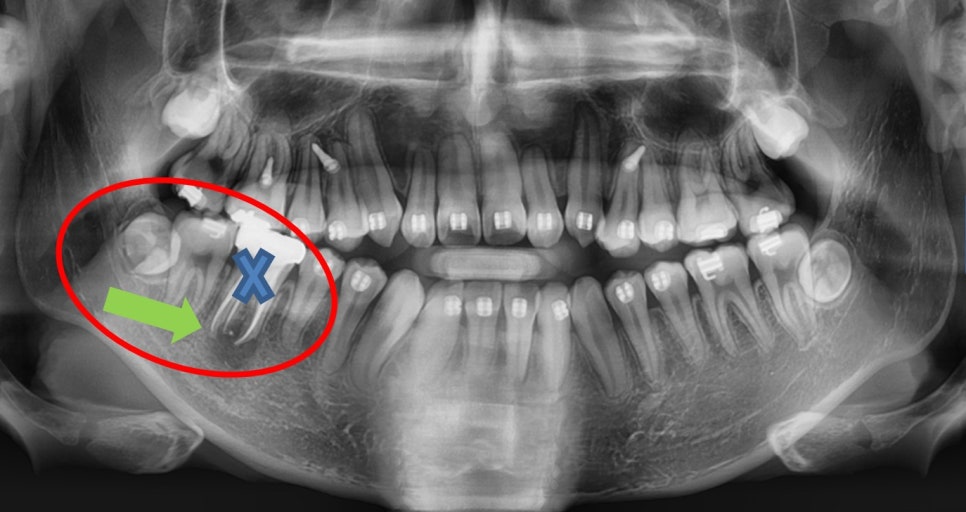

¾Æ·¡ ¾î±Ý´Ï¿¡ ¹®Á¦°¡ »ý°Ü¼­

Ä¡·á¸¦ Çϱ⠽±Áö ¾Ê¾Æº¸¿©

¹ßÄ¡Çϰí

½Ã°£ÀÌ Á» °É¸®´õ¶óµµ

µÚÀÇ »ç¶û´Ï¸¦ ¾ÕÀ¸·Î ´ç±â´Â Á¶Ä¡¸¦ Çϱâ·Î

ÇÏ¿´½À´Ï´Ù.

¿À¸¥ÂÊ ¾Æ·¡ ¾î±Ý´Ï¸¦ ¹ßÄ¡ÇÏ¿´°í

¹ßÄ¡ °ø°£ ÀüÈÄÀÇ Ä¡¾Æ¸¦ ¿òÁ÷¿©

°ø°£À» ¾ø¾Ö±â·Î ÇÏ¿´½À´Ï´Ù.